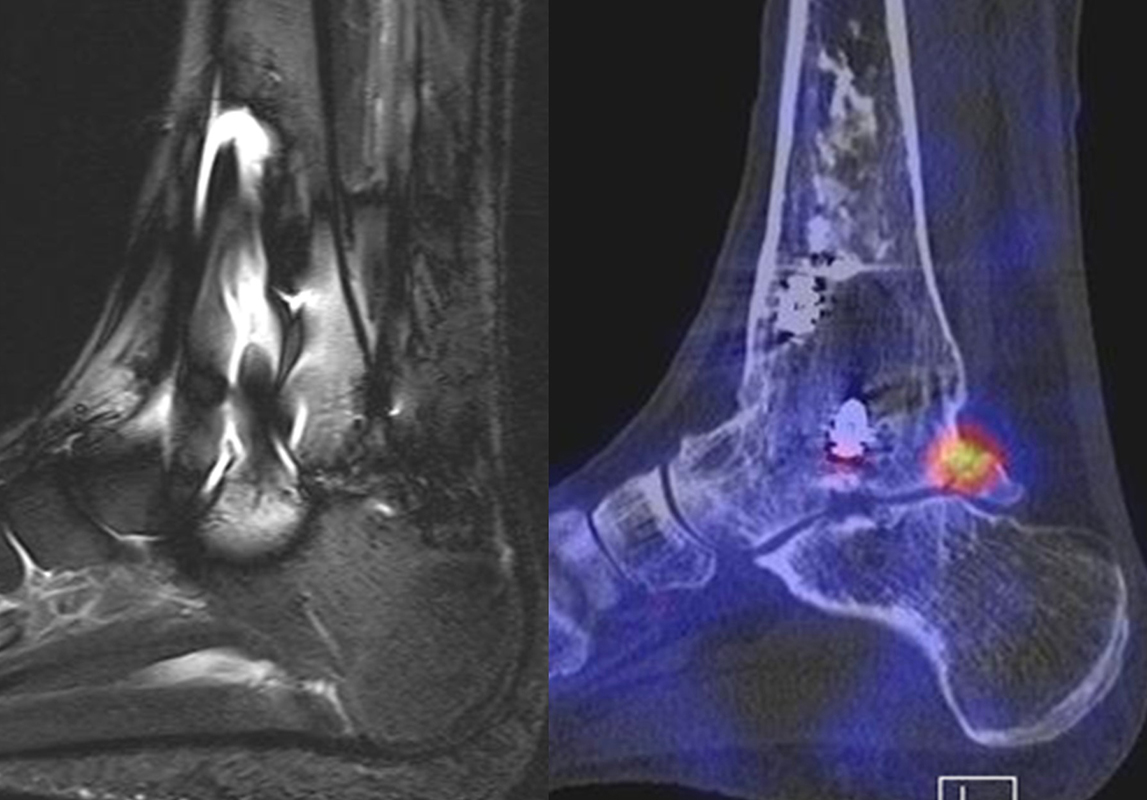

Abbildung 8.1. a bis f.: Patient mit Z. n. OSG-Distorsion vor 8 Monaten und konservativer Therapie. Anhaltende Schmerzen im Bereich des linken Innenknöchels. Im MRT bestand der Verdacht auf eine symptomatische kleine osteochondrale Läsion im medialen linken Talus (Abbildung 8.1. a und c). Zur weiteren Klärung erfolgte eine SPECT/CT 30 Tage später, welche jedoch im Gegensatz zur MRT eine fokale Mehrspeicherung an der tibialen Insertion des Deltabandes nachwies. Die Tatsache, dass die SPECT/CT spezifischer als die MRT symptomatische Bandläsionen detektieren kann wird untenstehend ausführlich thematisiert.

Abbildung 8.2. zeigt den Fall eines Patienten mit Verdacht auf ein knöchernes posteriores Impingement. Es bestanden Beschwerden dorsal bei Plantarflexion und ein Z. n. Distorsion des linken OSG vor 2,5 Jahren. Im MRT 2 Monate vor der SPECT/CT keine wegweisenden Befunde. Im SPECT/CT eindeutige fokal deutliche Mehrspeicherung im Bereich des Processus posterior tali.

Abbildung 8.3.a bis d demonstrieren Bilder einer Patientin mit Z. n. Arthrodese des linken OSG vor 6 Jahren. Das MRT ist bei ausgedehnten Metallartefakten nur bedingt aussagekräftig und weist nicht auf die auffälligen Befunde im SPECT/CT hin. Es bestehen sowohl fokale Stressreaktionen im Bereich eines Os trigonum und lateral im USG.

Abbildung 8.4.a bis d: Bilder einer Patientin mit chronischen Schmerzen im lateralen unteren Sprunggelenk links. Im MRT V. a. akzessorisches Knochenelement. Anamnestisch Beschwerden im Bereich des linken Sprunggelenkes seit 5 Monaten. Zuvor intensive sportliche Betätigung. Unter anderem tägliche atypische Belastung beider Füße durch Hinknien im Rahmen der Tätigkeit als Erzieherin. Diese Patientin hat nebenbefundlich bilaterale Akzessoria bzw. einen beiderseits angelegten Talus secundarius, der linksseitig jedoch nicht für die Symptomatik verantwortlich ist (die Bilder davon werden in Abbildung 3.5. gezeigt). Verantwortlich für die Symptomatik ist ein links posterolateral am Talus atypisches Knochenelement in einer Mulde mit engem Bezug zum unteren Sprunggelenk, DD atypisches laterales Os trigonum oder DD atypische Osteochondrosis dissecans. Die MRT konnte nicht differenzieren, wo die Schmerzursache genau lag. Im SPECT/CT (Abbildung 8.4.b und d) eindeutig fokale Mehrspeicherung im Bereich des atypischen Knochenelementes. Intraoperativ bestand der Aspekt einer Osteochondrosis dissecans.